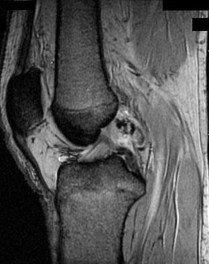

A 15-year-old male presents with deep knee pain awakening him at night. Radiographs show a permeative destructive lesion in the distal femoral metaphysis with a 'sunburst' periosteal reaction and Codman's triangle.

Biopsy confirms high-grade conventional osteosarcoma. What is the most critical prognostic factor for long-term overall survival in this patient?

Explanation

For localized high-grade osteosarcoma, the most important prognostic indicator is the histologic response to neoadjuvant chemotherapy. This is evaluated during the definitive resection. A 'good response' is typically defined as greater than 90% or 99% tumor necrosis. Patients who achieve this level of necrosis have a significantly improved disease-free and overall survival rate compared to 'poor responders' who have extensive viable tumor cells remaining.